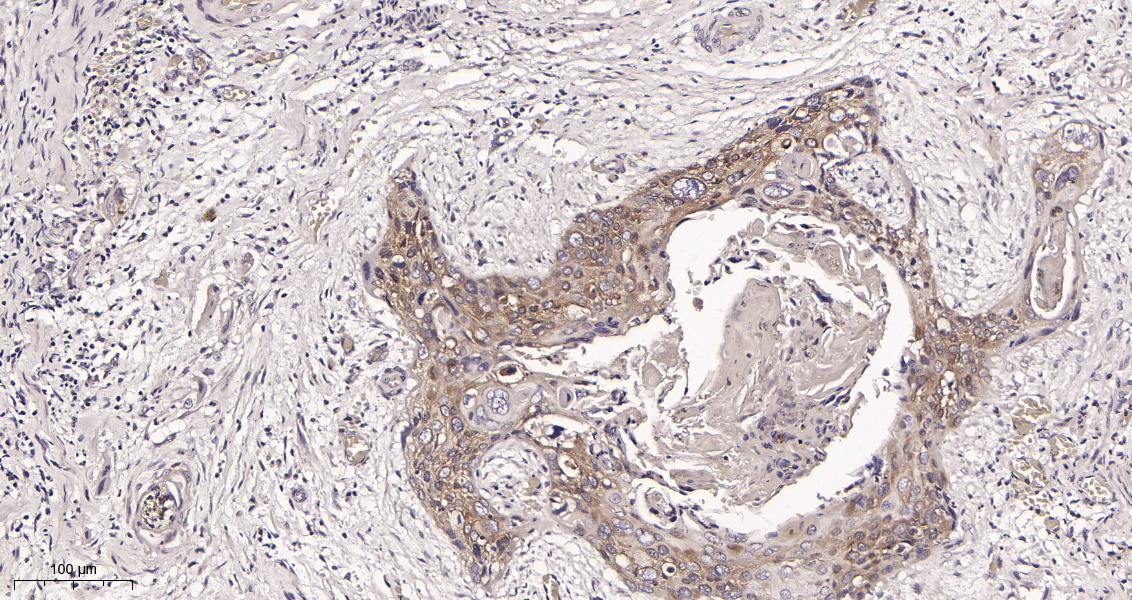

产品名称RIP (13D15) Rabbit Monoclonal Antibody

推荐应用WB,IHC-P,IF-P,IF-F,IF-ICC,ELISA

稀释度IHC-P 1:200-1000, WB 1:1000-5000, IF-P/IF-F/IF-ICC 1:200-1000, ELISA 1:5000-20000